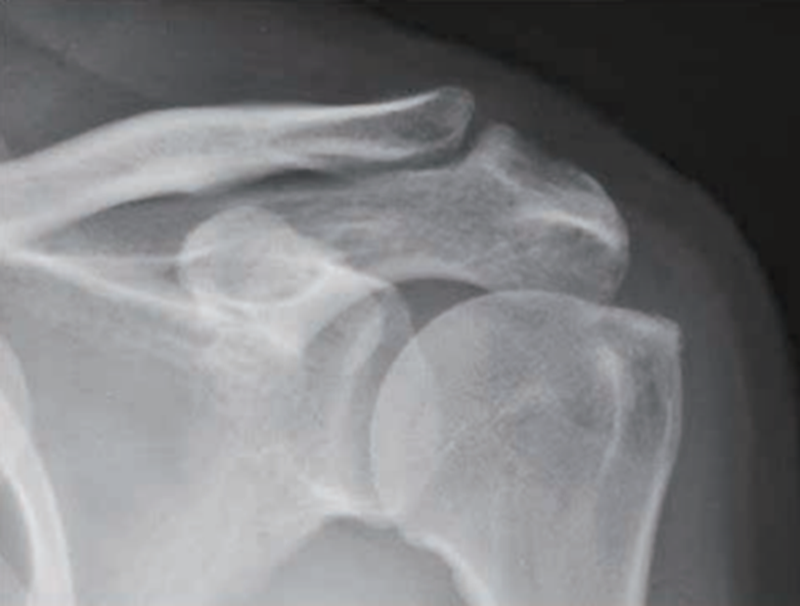

X线检查用来评估肩峰形态、肱骨头和肩盂、肩峰的关系。在正位片上,大结节的硬化、增生及局限性骨密度降低,甚至囊肿形成,都是肩袖损伤的重要间接征象(图3)。

图3 大结节增生硬化X线影像